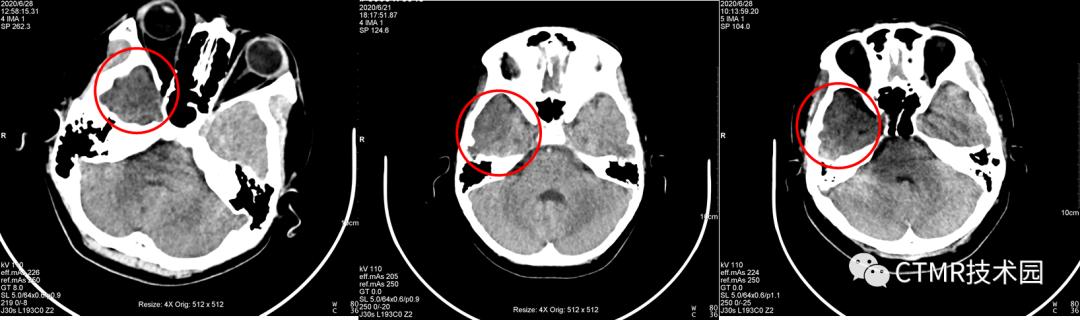

上周我在此机器值班,因为此伪影一直在我脑子里存留,平时在上 Philips Brilliance 64 CT 时,注意观察了下它扫描颅脑的螺距,非常小,可供选择的范围很小,最大可选 0.399。飞利浦的机器比较好的一点就是,它固化了 Scan type,不同的扫描部位/检查方法定义不同的 Scan type,那么在 Brain 扫描类型下,再进一步限制 Collimitation,螺距,Rotation time 等一系列参数,以期获得最佳的的图像质量。那么我就在此机器上尝试选用小螺旋扫描,最小可以改到 0.35,扫了几个病人,伪影完全消失!可以证明,在西门子这台机器上采用大螺距扫描是不合理的,应当也使用小螺距扫描。而且采用小螺距 DLP 还降低了,那么可以进一步增大 QRM,以期获得更好的图像。

而且选用 0.35螺距 eMode 是绿色;如果用 1.1 螺距,那么 eMode 是黄色;如果应用 Adjust,eMode 也变成绿色,且此时当前病人配给的螺距为 0.9,那么它好吗?其实扫描出来的图像大多还是有伪影(从本文开头贴的图片中,有好几个都是 Adjust 后匹配螺距扫描出来的伪影图像)。

问题1:为什么都是经常出现在右侧呢?因为颅脑大致头足范围都差不多,且都是从头向足螺旋扫描,那么螺旋扫描时可能恰好采集伪影区域层块时,是从头左侧先转的一整圈,那么就导致了右侧不在一个完整的环上,因为转过来时已经跑到下一层块了。其实有时病人以 1.1 螺距扫描是没有伪影的,比如头颅扫描范围有所偏差时,那么上一圈扫描结束位置恰好在前 A 位置,那么伪影这一层块扫描时时恰好左侧与右侧颞部基本都在一整圈范围内。这样的情况也是会出现的,那么此时图像上右侧就不会出现明显的暗区伪影。为了验证如此,我还将扫描顺序更改了下,按足向头扫描(如下图),恰恰暗区伪影经常出现在左侧。当然球管到底是怎么转的,如果能够打开机架外壳,仔细看看就好了。